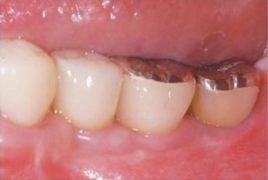

Przeszczep kości. W niektórych sytuacjach jest to jedyna skuteczna metoda odbudowy zanikłej kości. Zabieg polega na pobraniu fragmentu tkanki kostnej z innego miejsca jamy ustnej (albo przy większych przeszczepach z biodra) i następnym umocowaniu go w miejscu odbudowywanym. W ciągu kilku miesięcy następuje wgojenie się przeszczepu -€“ zamienia się on w pełnowartościową kość.